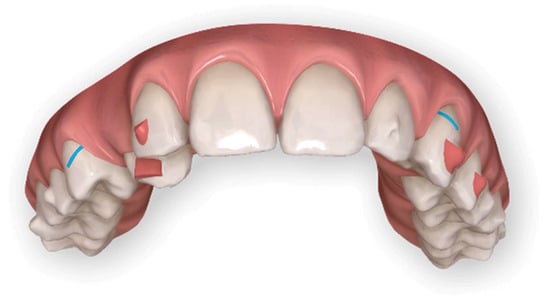

At the first Clincheck®, the use of an eruption compensator was planned in order to link the displaced canine to the aligner, through an elastic ligature, thus facilitating the desired movement. Bite ramps are usually placed in order to disocclude the upper and lower arches and increase the movement of the canine from the palatal to the vestibular side (Figure 5 and Figure 6).

Figure 5.

First Clincheck® and first set of aligners to create space, reach alignment and levelling of both arches. The use of elastics and button as auxiliaries to promote the movement of the impacted canine.

Figure 6.

Progress of treatment with mechanics of elastics.